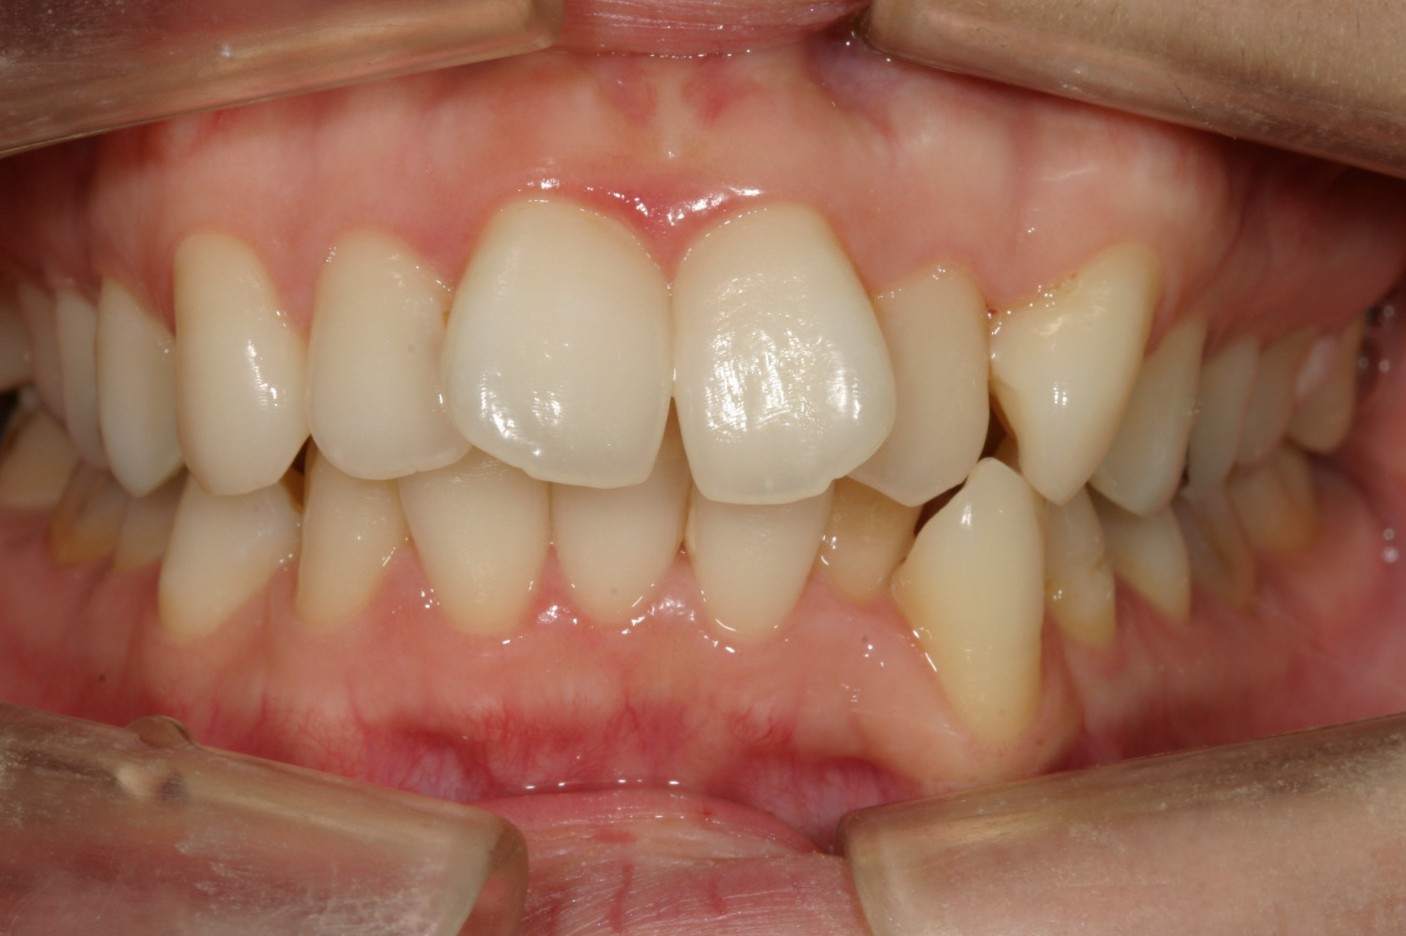

前歯のガタガタと翼状捻転を改善したい。

翼状捻転がきついですね~

左側犬歯の飛び出しが目立ちます。

少し出っ歯感が気になります。